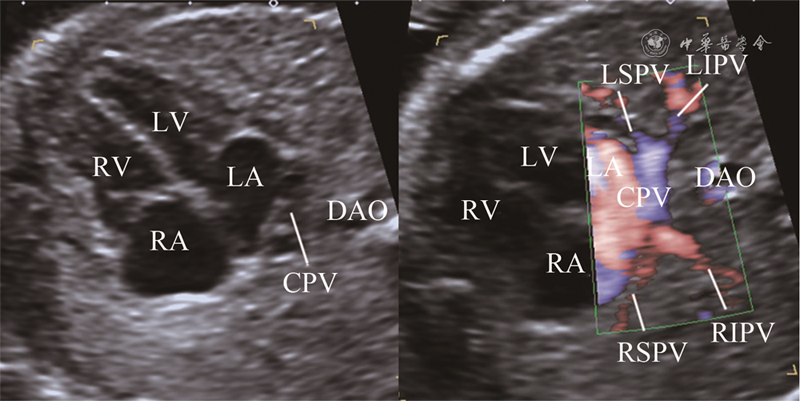

图1 正常胎儿肺静脉区域血流分布超声图像。左图白线将胸部横切面肺组织大致分为4个区域,左侧前上部1/2肺野、左侧后下部1/2肺野、右侧前上部1/2肺野、右侧后下部1/2肺野;右图彩色血流显示左上肺静脉远端分支分布于左侧前部1/2肺野,左下肺静脉远端分支分布于左侧后部1/2肺野,右上肺静脉远端分支分布于右侧前部1/2肺野,右下肺静脉远端分支分布于右侧后部1/2肺野(对应动态图1),4条肺静脉近心端呈螃蟹征插入左侧心房壁,分支间距较大

图2 胎儿心上型完全型肺静脉异位引流超声图像。右图胸部横切面彩色血流显示左上肺静脉远端分支分布于左侧前部1/2肺野,左下肺静脉远端分支分布于左侧后部1/2肺野,右上肺静脉远端分支分布于右侧前部1/2肺野,右下肺静脉远端分支分布于右侧后部1/2肺野(对应动态图2),4条肺静脉近心端均未回流入左心房,呈现左心房后方汇聚征,肺静脉分支间距减小;左图为二维超声对比图像